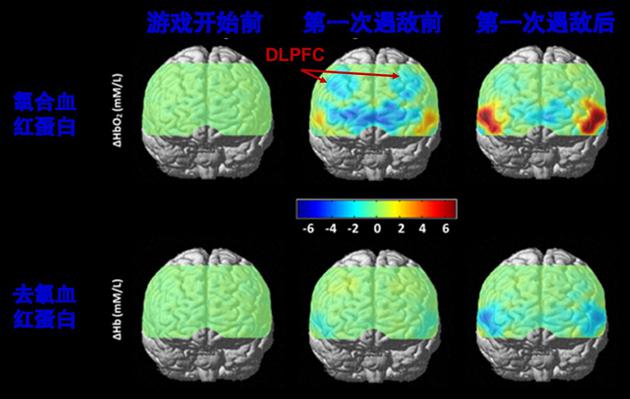

德国科学家研究发现:青少年在两个月内每天玩至少半个小时的《超级玛丽》,其右侧大脑的背外侧前额叶区(DLPFC)和小脑(cerebellum)中的灰质密度会增加,提示这些脑区在玩游戏的过程中得到了锻炼有趣的是,我们自己最近的一项研究表明:在校大学生在玩《英雄联盟》这款游戏时,其DLPFC大多数时候却是处于一种抑制的状态。这似乎跟德国科学家的研究结果矛盾了。如何解释这个矛盾呢?我们猜想,这可能与游戏种类有关。在德国科学家的研究中,青少年玩的大多是《超级玛丽》这一类的单人冒险类游戏,而我们研究的《英雄联盟》是多人在线动作类游戏。玩家在不同种类游戏中所采用的策略、进行的游戏操作以及可能得到的奖赏都是不一样的。这可能就决定了DLPFC在游戏中是激活还是抑制,是得到了锻炼还是被“关机”了。比如,我们发现《英雄联盟》玩家在游戏中击杀对手后DLPFC会出现最为显著的抑制,这可能与玩家那一瞬间正处于一种“杀红眼”的状态有关。

大学生玩家玩《英雄联盟》时大脑的实时功能活动监测结果。跟游戏开始前(左图)相比,游戏开始后双侧背外侧前额叶(DLPFC)中的氧和血红蛋白(HbO2)水平显著下降(中图),提示脑区的功能可能受到了抑制。遇到敌人并进入战斗后有所恢复(右图)

大学生玩家玩《英雄联盟》时大脑的实时功能活动监测结果。跟游戏开始前(左图)相比,游戏开始后双侧背外侧前额叶(DLPFC)中的氧和血红蛋白(HbO2)水平显著下降(中图),提示脑区的功能可能受到了抑制。遇到敌人并进入战斗后有所恢复(右图)当DLPFC功能受到抑制时,人的理性思考和控制能力就会变弱;相应的,外界刺激的诱惑就会变强。天使与魔鬼交战的天平就会向魔鬼一侧倾斜,从而使我们 “欲罢不能”。青少年期正是大脑前额叶发育的关键时期。在这个时期,前额叶要学习建立、适应并运用现实世界的各种规则;如果此时沉溺于游戏,大脑尤其是DLPFC就可能按照虚拟世界的规则来进行塑造,这会为其之后的学习和生活产生带来很多负面的影响。